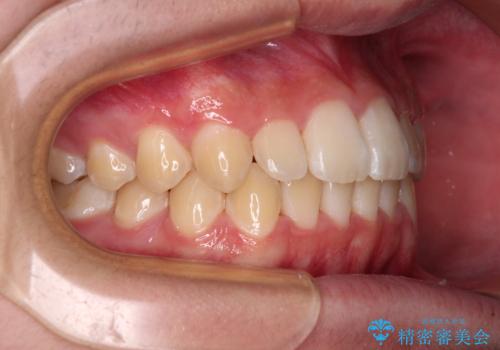

「しっかりと装着する」が実行でき、高校3年生の秋には治療を終えることができました。

入試時期に入ると、後戻り防止のリテーナー装着が疎かになる可能性があったり、リテーナーが壊れてしまった場合すぐに来院できなかったりというリスクがあったため、下顎前歯の舌側をワイヤーで固定することとしました。